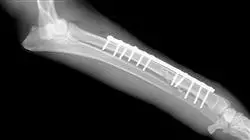

A equipa docente deste Curso de Especialização em Métodos de Fixação de Fraturas fez uma seleção cuidadosa das diferentes técnicas de ponta para profissionais experientes que trabalham na área da Medicina Veterinária. Em concreto, esta especialização centra-se no estudo dos fixadores externos esqueléticos e dos fixadores circulares, da pregagem intramedular e das placas e parafusos ósseos.

A fixação externa das fraturas consiste na utilização de um suporte rígido colocado fora do corpo e ligado ao osso por agulhas através da pele (transcutânea). A técnica de colocação comparada com outros métodos de osteossíntese interna mostra que a fixação externa melhora o ambiente biológico~, preserva os tecidos moles e a irrigação, acelera a cicatrização, diminui o risco de infeção e reduz o tempo operatório.

O fixador externo proporciona uma fixação estável das extremidades ósseas sem necessidade de implantes na linha de fratura ou imobilização das articulações vizinhas, sendo por isso particularmente adequado para fraturas abertas, expostas ou infetadas. Permite comprimir, neutralizar ou distrair os filamentos ósseos em função das necessidades da patologia.

A colocação de pregos intramedulares (IM) em fraturas de cães e gatos teve início na década de 40. A sua popularidade aumentou devido aos progressos da anestesia, das técnicas assépticas, dos antibióticos e da consciencialização dos veterinários e dos donos de animais de que, na maioria dos casos tratados, a reparação era satisfatória.

Assim, o prego intramedular é, desde há muito, o implante mais utilizado em Medicina Veterinária, porque é colocado na cavidade medular e torna-se resistente à flexão em todas as direções. A sua resistência está relacionada com o seu diâmetro e com a sua capacidade de limitar o movimento dos fragmentos ósseos fraturados. É o sistema de fixação mais comummente utilizado para cães e gatos.

Nos últimos 20 anos, a fixação de fraturas com implantes rígidos de fixação interna, como as placas, evoluiu enormemente. Poder-se-ia falar de oito ou nove sistemas diferentes, mais amplamente reconhecidos, de fixação de fraturas por meio de placas. Neste caso, a especialização centrar-se-á nas mais utilizadas a nível mundial.